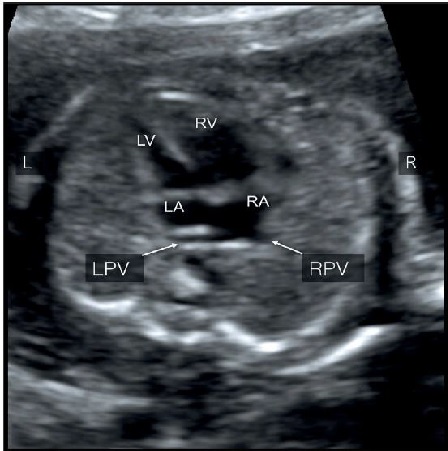

Hình 2: Mặt cắt ngang 4 buồng tim: Hình ảnh bất thường hồi lưu tĩnh mạch phổi toàn phần (TAPVR) thể trên tim (type I: supracardiac). Hình phóng to phía sau tâm nhĩ trái B và C. Lưu ý tâm thất phải (RV) và nhĩ phải (RA) lớn hơn tâm nhĩ trái (LV) và thất trái (LA) do tĩnh mạch phổi gián tiếp đổ vào nhĩ phải. Cả hai tĩnh mạch phổi phải (RPV) và tĩnh mạch phổi trái (LPV) đều không đổ vào nhĩ trái mà đổ vào tĩnh mạch hội lưu (confluent vein) “mũi tên rỗng”.

Hình 8: (A) Hình ảnh Doppler màu mặt cắt ngang ngực thai thi có bất thường hồi lưu tĩnh mạch phổi toàn phần (TAPVR). Chú ý tĩnh mạch phổi phải (RPV) và tĩnh mạch phổi trái (LPV) không đổ vào nhĩ trái mà đổ vào tĩnh mạch thu thập (confluent vein), ngăn cách với nhĩ trái bởi một dải mỏng. (B) Tịnh tiến đầu dò về phía đầu thai nhi thấy hình ảnh mặt cắt ngang tĩnh mạnh đứng dọc (vertical vein) ở trong lồng ngực (mũi tên rỗng).